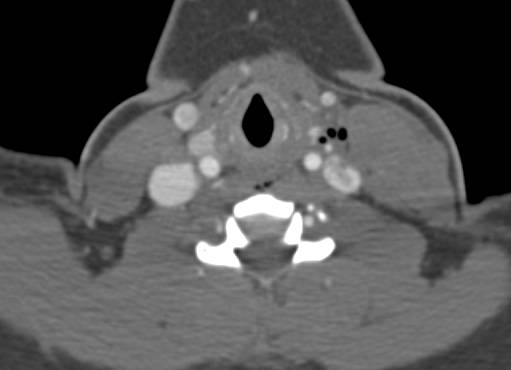

Thrombus Seen in the Aortic Arch